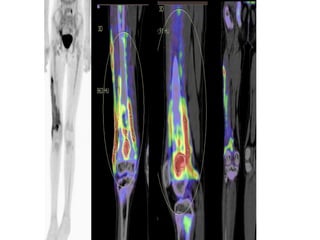

• Técnicas de imagen funcionales (p. ej., gammagrafía ósea,

tomografía por emisión de positrones [PET], etc.).

• Radiografías

• Gammagrafía

SánchezAguilar, M., García Jiménez, R., & Borrego Dorado,I. (2017). Miositis osificante: gammagrafía ósea y tomografía por emisiónde positrones/tomografía computarizada con 18F-desoxiglucosa.Reumatologia Clinica. https://doi.org/10.1016/j.reuma.2017.01.017

DIAGNÓSTICOS

• Diferenciales

• Se incluyen tumores malignos como el

linfoma, el osteosarcoma o el

rabdomiosarcoma.

• Los métodos diagnósticos de imagen

difieren en sensibilidad y especificidad

dependiendo de la fase madurativa del

proceso en el que sean utilizados

MÉTODOS DE

DIAGNÓSTICO

En radiología no observaremos imágenes sugerentes de

MO hasta pasadas de dos a cuatro semanas del inicio de

los síntomas.

la ecografía es capaz de detectar cambios tempranos en

los tejidos blandos, precisa de completar el estudio con

otras pruebas de imagen que confirmen los patrones de

osificación característicos de la MO

La RMN es la técnica de imagen de elección para la

evaluación de tejidos blandos, y nos permitirá delimitar la

lesión.